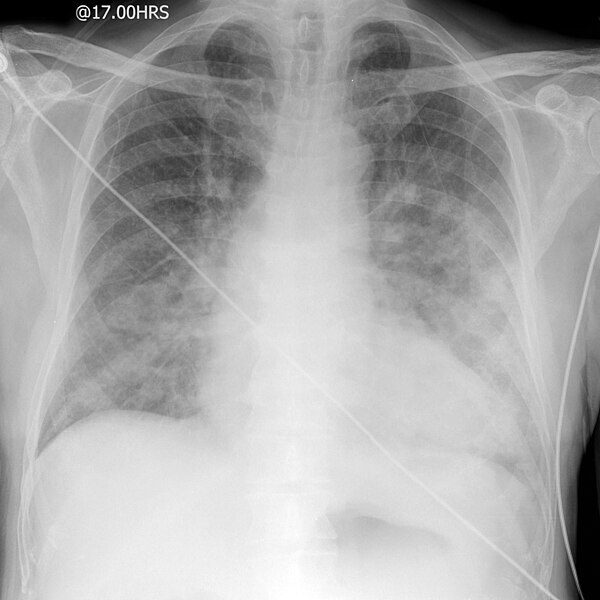

what does this CXR show?

A

pneumonia

- right upper zone consolidation